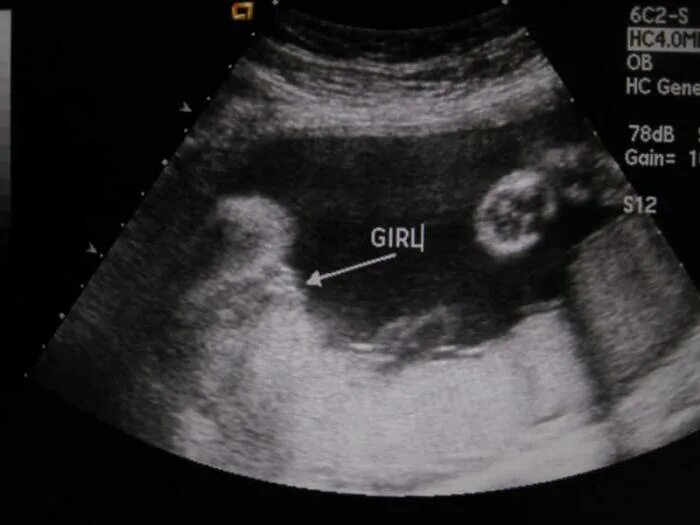

Ошибается ли скрининг